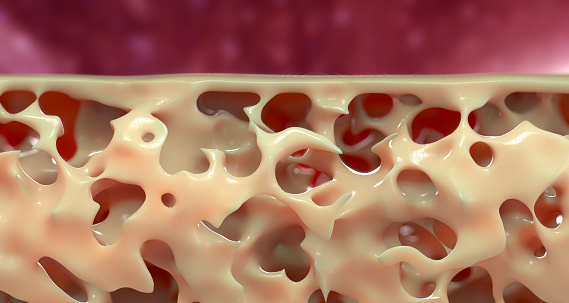

Concerned about your bone health? You should be. The sooner you start the better. Your risk for osteoporosis, where your bones become fragile and porous, has a lot to do with the bone mass you’ve developed in your 20s and 30s and what you’ve done to prevent losing that bone mass later on. Bones, like the ...click here to read more